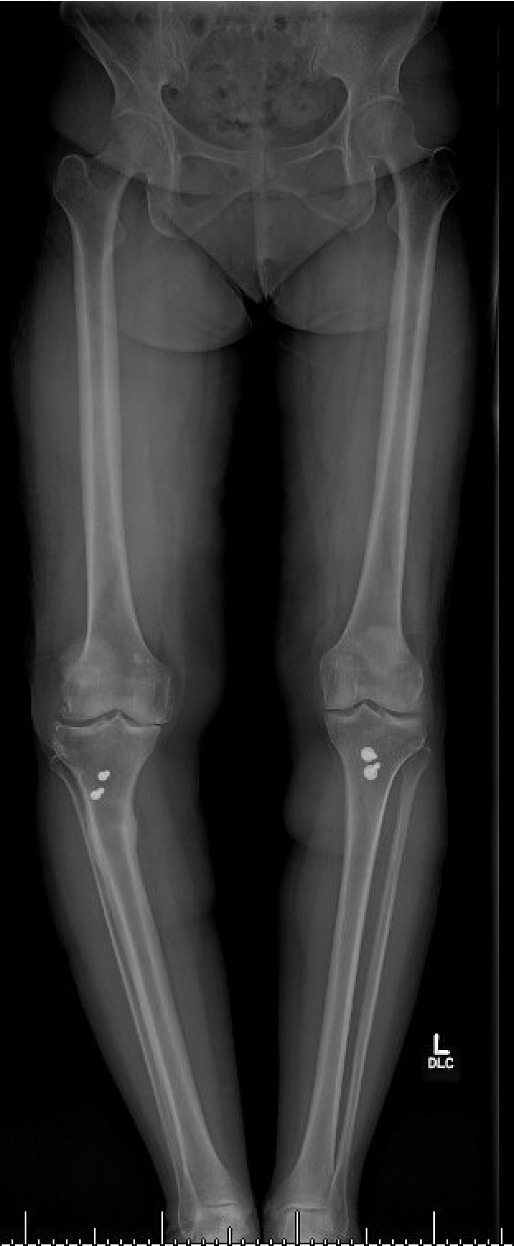

Pre-operative radiographs demonstrated Kellgren-Lawrence grade 4 tricompartmental osteoarthritis, 12° of tibial varus, a 22 mm deviation of the mechanical axis toward the medial side of the knee center, and an apex of angulation located 6 cm below the joint line (Figures 1 and 2). A follow-up computed tomography scan confirmed the absence of rotational malunion.

The total estimated blood loss was 300 mL, and no transfusion was required. The patient tolerated oral intake on the evening of surgery, completed her first physiotherapy session the following morning, and ambulated fifty feet with a rolling walker while wearing the hinged knee brace locked in extension. Following ambulation, full length lower extremity films were re-obtained, demonstrating neutral mechanical hip–knee–ankle axis (Figure 5). She was discharged home on post-operative day two with acceptable pain control and an incision that was clean, dry, and intact.

Quantitative range-of-motion and outcome-score data are summarized in Table 1. At the two-week clinic visit the incision was fully healed and sutures were removed. The patient continued full weight bearing in the brace. By six weeks the osteotomy displayed bridging callus across the osteotomy site (Figure 6), the brace was discontinued, and she achieved an unrestricted gait pattern without assistive devices. Four months after surgery, the patient had resumed activities such as tennis and reported no pain or swelling. Radiographs at that time demonstrated complete cortical union without any interval changes in alignment (Figure 7). At the nine-month assessment she reported hiking up to five miles and skiing on groomed slopes without limitation. Imaging showed continued consolidation of the osteotomy and stable components (Figure 8).